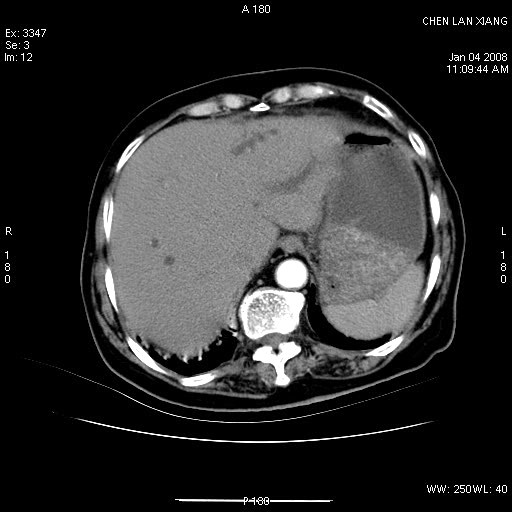

标题: CT11180:女,76岁,腹痛3-4天 [打印本页]

女,76岁,腹痛3-4天,b超示:肝内实性肿物,胆囊强回声,胆总管扩张.

考虑:1、胆总管下端结石伴梗阻性肝内外胆管扩张(肝左叶外侧段肝内胆管多发结石、胆管炎);

2、肿囊癌累及肝,不除外 黄色肉芽肿性胆囊炎。

1 胆总管末端结石伴肝内胆管结石,肝内外胆管扩张。2 胆囊扩大,胆囊壁不规则增厚,内见软组织密度影。考虑:慢性胆囊炎,不除外胆囊癌!

标题: 肝右叶病灶

胆囊癌侵犯肝右叶?

1)胆囊癌伴肝脏转移。2)胆总管下端结石、肝内胆管结石伴肝内外胆管扩张。